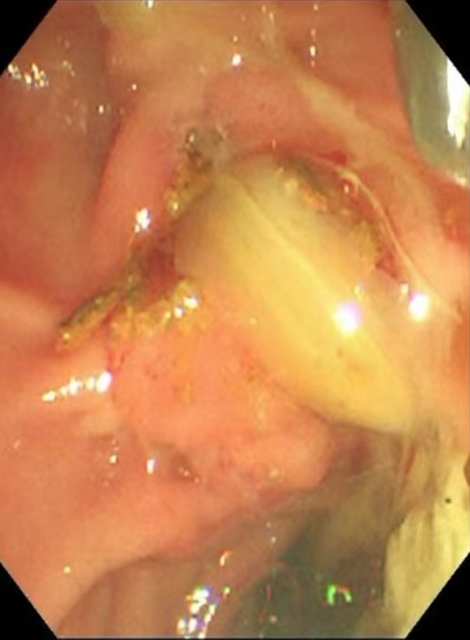

内镜到达十二指肠乳头时,切开乳头的瞬间,大量白色脓液喷涌而出(证实胆道高压、感染极重);随后用球囊扩张乳头(扩大开口),顺利取出嵌顿的结石。

内镜逆行胰胆管造影的关键操作是乳头切开引流+取石:医生用微型电刀切开狭窄的乳头(类似“扩大下水道口”),再用网篮或球囊取出结石。从切开到取石,通常仅需10-30分钟,能迅速降低胆道压力,让淤积的脓性胆汁通过切口及鼻胆管流出体外—这是控制感染、逆转休克的关键。

内镜逆行胰胆管造影全程在X光和内镜直视下完成,医生能清晰看到结石位置、乳头形态,避免盲目操作。即使结石嵌顿严重(像"卡在墙缝里的石块"),也能通过球囊扩张或机械碎石取出,成功率高达90%以上。